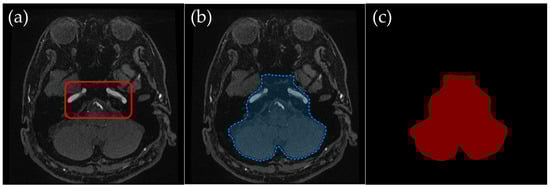

2.3.3. Temporal–Occipital Junction Level: Retaining Internal Carotid and Vertebrobasilar Arteries

Temporal–Occipital Junction Level (Figure 4): Only the internal carotid artery and the occipital lobe region were retained in the ROI. This slice range typically represents a section just inferior to the Circle of Willis, where the internal carotid arteries and the vertebrobasilar system begin to converge near the center of the brain. This level was particularly important for ensuring clear visualization of vertebrobasilar arteries, as overlapping signals from extracranial vessels can obscure diagnostically relevant structures in MIP images.

Figure 4. Example of manually annotated training data at the temporal–occipital junction level. (a) Original TOF-MRA axial image (inside red line indicates internal carotid arteries and vertebrobasilar arteries). (b) Manually defined region of interest (ROI) in blue, excluding the external carotid artery and non-intracranial structures. (c) Corresponding indexPNG mask for semantic segmentation training.